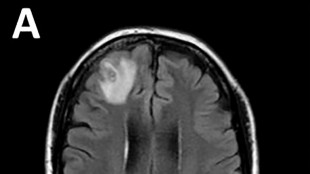

La commotion cérébrale, l'ennemi "insidieux" des soldats ukrainiens

À 15 km de la ligne de front de Bakhmut, dans l'est de l'Ukraine, un véhicule de combat d'infanterie s'arrête en déchirant le silence nocturne. En sort Andrei, claudiquant et le regard hagard.